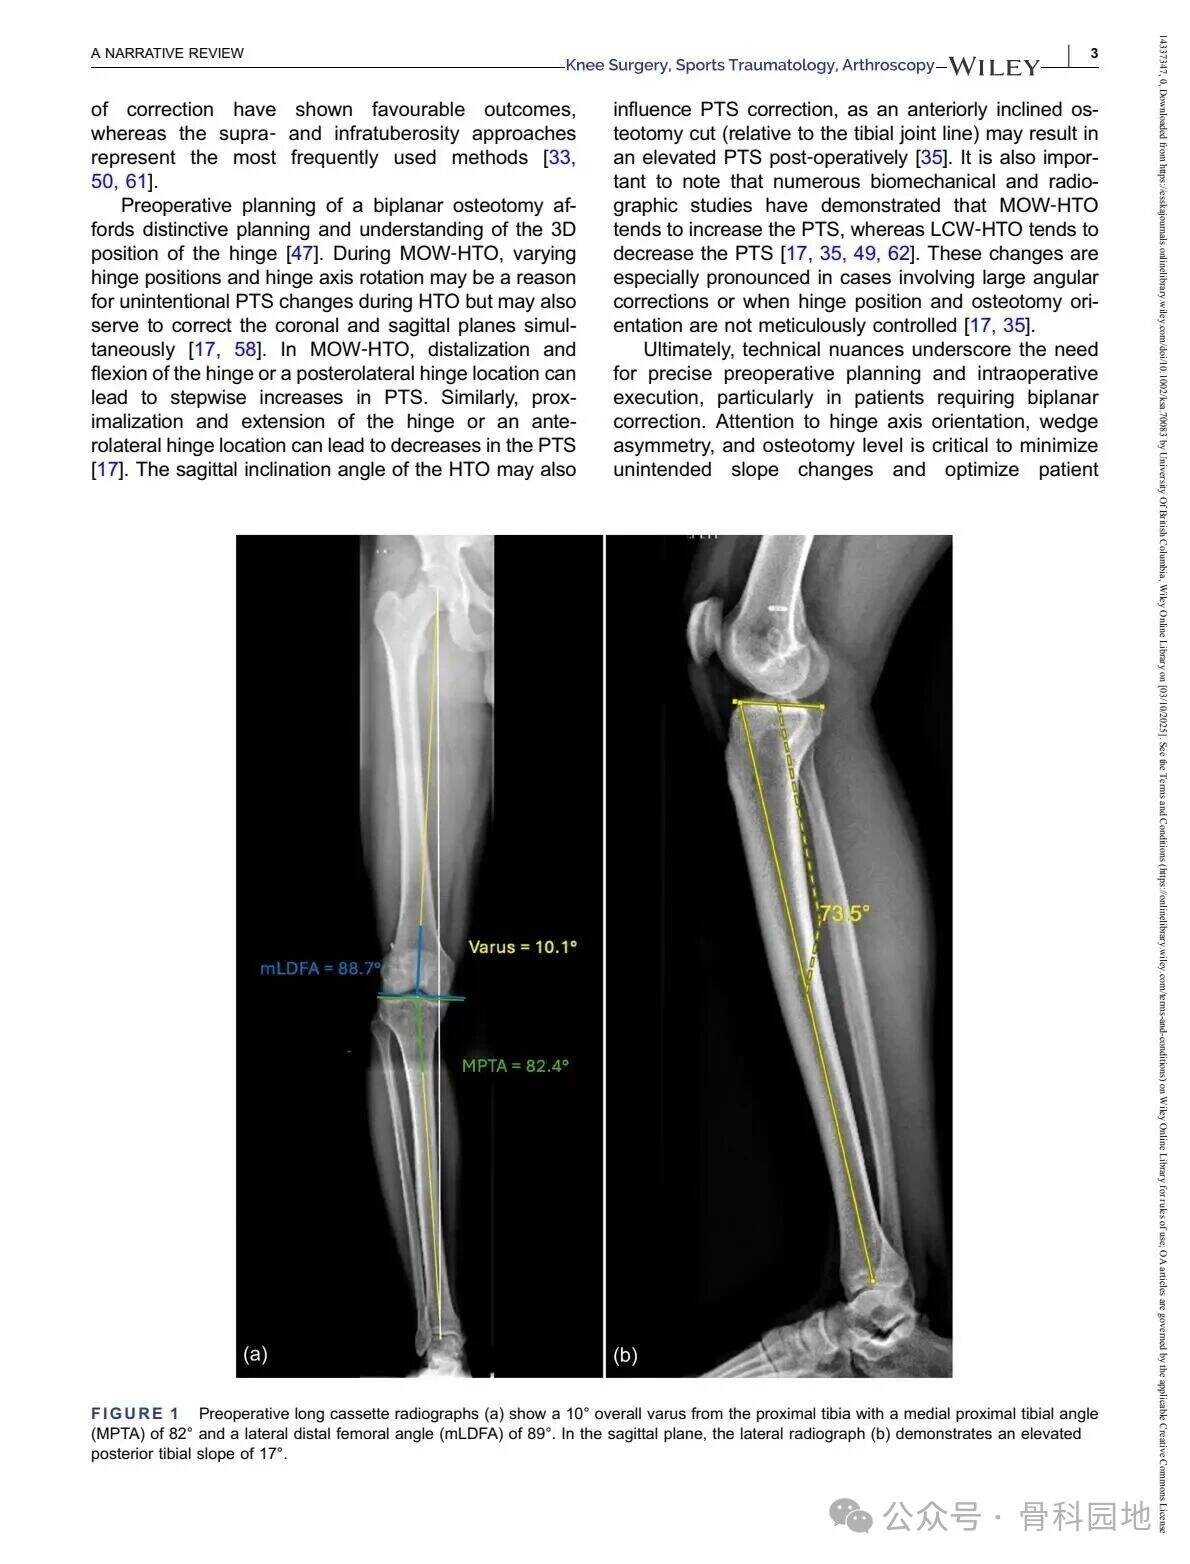

Čeprav konvencionalna visoka tibialna osteotomija (HTO) predvsem obravnava nepravilno poravnavo v koronalni ravnini, pomembnost poravnave v sagitalni ravnini – zlasti posteriornega tibialnega naklona (PTS) – ni mogoče prezreti v primeru nesposobnosti križnih vezi. Kombinirane nepravilnosti v koronalni in sagitalni ravnini so razmeroma redke in predstavljajo posebne kirurške izzive. Ta narrativni pregled povzema ustrezno literaturo ter predstavlja tehnične strategije za obravnavo zapletenih dvoravninskih nepravilnosti s pomočjo primerov iz prakse in razprav o različnih tehnikah.